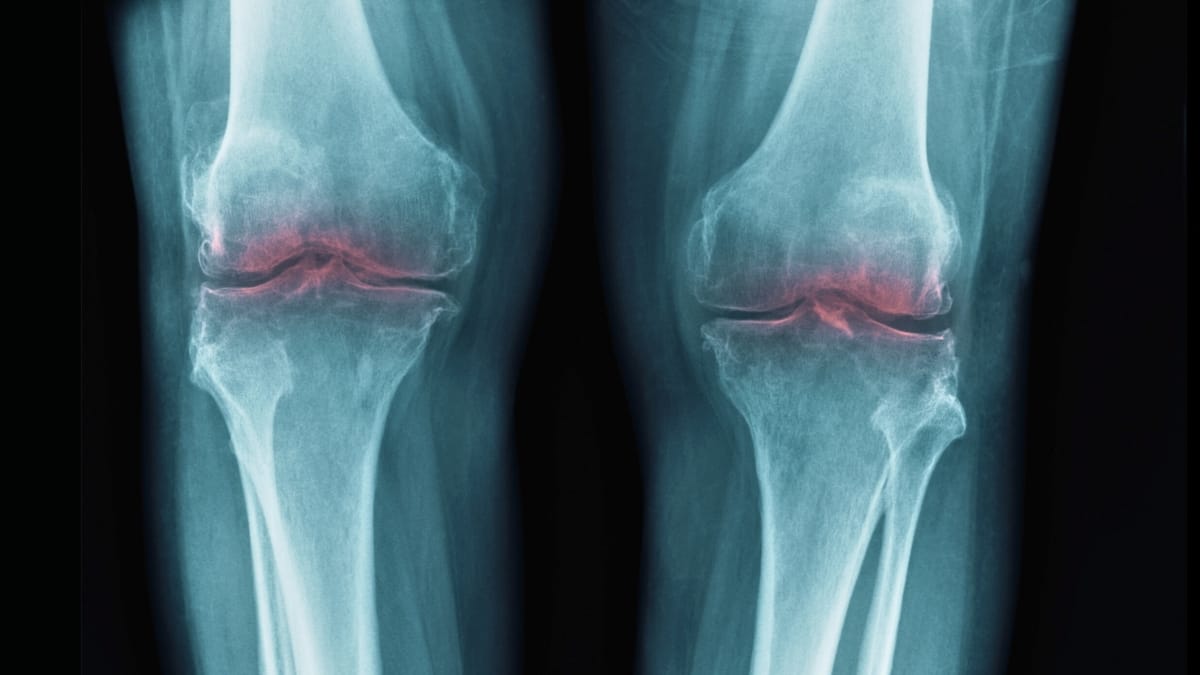

Um estudo recente identificou uma proteína associada ao envelhecimento como um fator crucial na degeneração da cartilagem, oferecendo novas perspectivas para o tratamento da osteoartrite. A pesquisa, realizada por cientistas da Universidade de Stanford, sugere que a inibição dessa proteína pode restaurar a mobilidade e reduzir a dor em idosos.

A proteína 15-PGDH, amplamente associada ao envelhecimento, aumenta sua presença no organismo à medida que as pessoas envelhecem, interferindo nos processos de reparo tecidual e na redução da inflamação. Este estudo demonstrou que a degradação da cartilagem, especialmente no contexto da osteoartrite, está ligada ao aumento dessa proteína, que afeta a estrutura do colágeno, fundamental para a saúde articular colágeno.

Em experimentos com camundongos idosos, a aplicação de um inibidor de 15-PGDH resultou no espessamento da cartilagem do joelho, que havia se desgastado anteriormente. Além disso, em testes com camundongos jovens que sofreram lesões, o inibidor impediu o desenvolvimento da osteoartrite, mostrando que a intervenção pode ser eficaz na proteção contra os efeitos típicos de lesões articulares Science.

A pesquisa também incluiu amostras de tecido humano de pacientes submetidos a cirurgias de substituição de joelho. Os resultados mostraram sinais claros de regeneração da cartilagem, que se tornaram mais rígidas e apresentaram menos inflamação. A mudança na expressão gênica das células presentes na cartilagem sugere que a abordagem pode ter um impacto clínico significativo na regeneração de tecidos disse a cientista ortopédica Nidhi Bhutani.